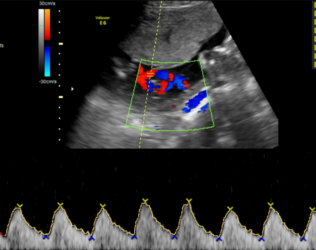

4.分娩前超声检查:超声重点观察指标包括:胎方位、胎儿大小、胎盘及胎儿循环、羊水量、胎盘成熟度、有无胎盘早剥或前置胎盘、脐带有无绕颈、脱垂等。这些指标对临产时医师选择正确的分娩方式,对母亲及胎儿健康平安至关重要。尤其对在整个孕期从未接受超声检查的准妈妈,为了母子的平安,分娩前务必接受一次超声检查。